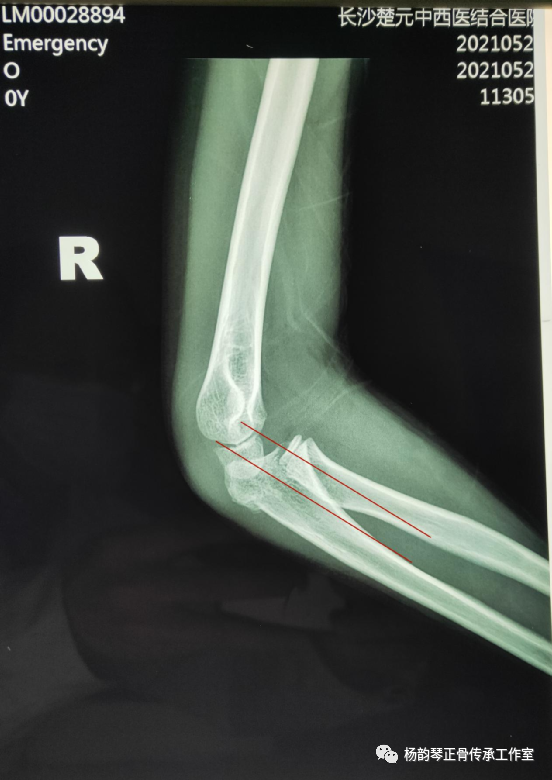

辅助检查:X线片:右尺骨近端骨折,右桡骨头脱位。

孟氏骨折特别容易漏诊的就是桡骨头脱位,此患者从侧位片上看可以看到桡骨近端纵轴线没有通过肱骨小头中心,提示肱桡关节匹配不良,桡骨头脱位。除非直接暴力导致尺骨骨折,一般单纯尺骨骨折比较少见,临床上看到尺骨骨折就必须密切关注肱桡关节匹配情况,桡骨头脱位后可能自动还纳,若此时忽略对桡骨头的固定,可能发生再脱位。所以即使X线片仅见骨折而无脱位,一般最好也按孟氏骨折来处理,避免漏诊。